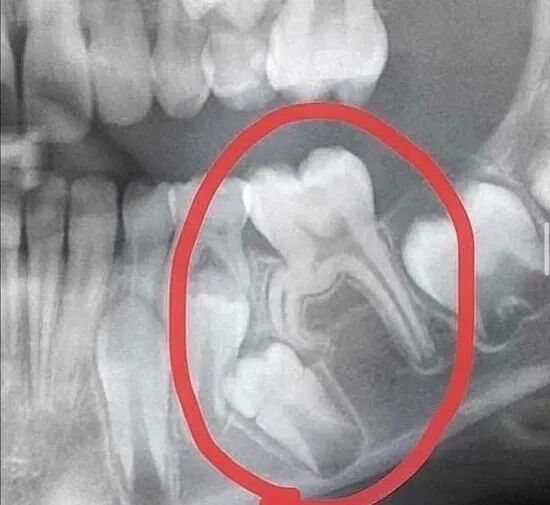

我不是牙医,但我能看出这颗牙很嚣张...